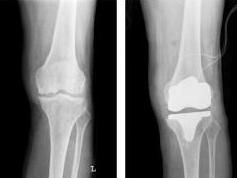

目前,膝關節置換和髖關節置換是人工關節置換術中最常見的兩類手術,其十年的成功率已經超過90%,更有80%以上的患者可以正常使用植入的假體長達20年以上,甚至伴隨其終生。除此以外,肩關節、肘關節、踝關節等關節置換也在不斷發展,取得了良好的中、長期結果。隨著生物材料與外科技術的進步,陸續出現了腕關節、指間關節、跖趾關節等小關節置換術,為患有嚴重小關節疾病的患者帶來了希望。

人工關節置換術主要目的是緩解關節疼痛,糾正關節畸形,恢復關節功能,提高患者生活質量。

人工關節作為一種器官替代物,必然存在磨損與失敗的問題,但現代人工關節假體已經能夠達到良好的長期生存率。英國國立衛生院(NHS)提出了人工關節置換術的標準,即十年的成功率至少達到90%以上,稱為NICE標準。而在臨床實踐中,已有大量數據表明通過良好的手術技術,選擇合適的人工關節假體,在患者的充分配合下,人工關節置換,特別是膝、髖關節置換的20年的優良率可以達到90%以上。